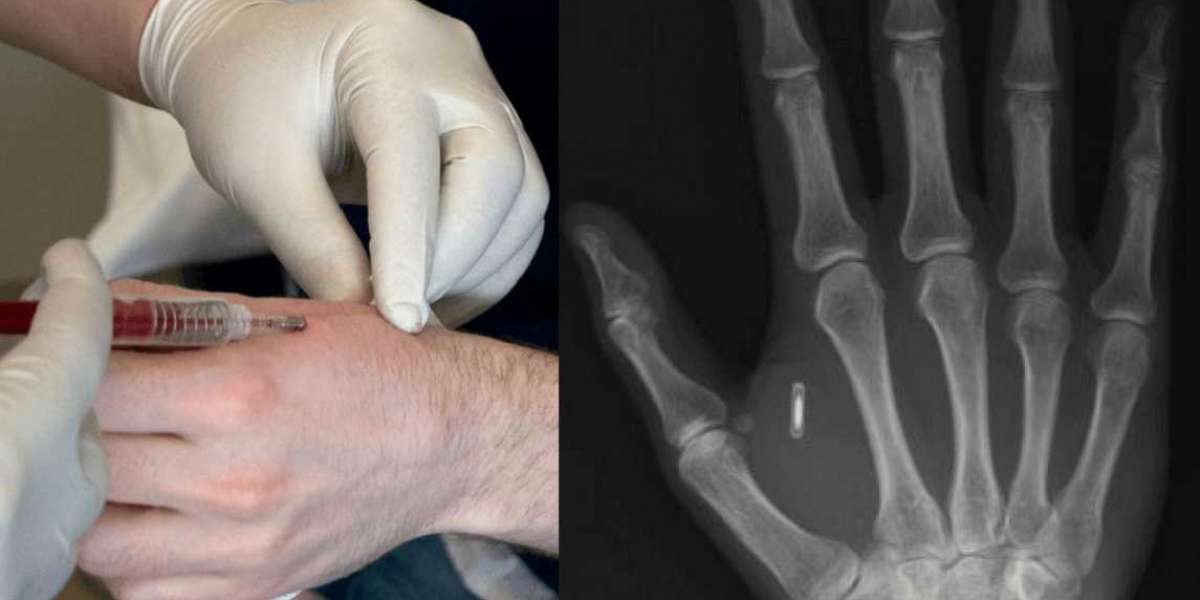

image